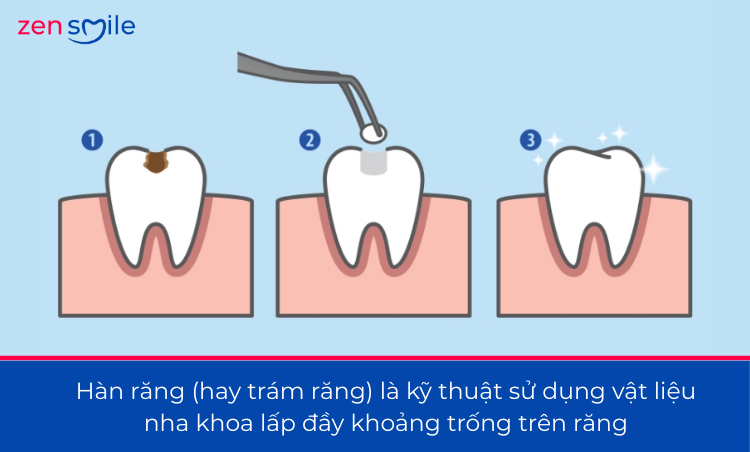

1. Hàn răng vĩnh viễn là gì?

Hàn răng vĩnh viễn là phương pháp điều trị nha khoa phổ biến, giúp phục hồi hình thể và chức năng ăn nhai cho răng bị sâu, mẻ hoặc tổn thương nhẹ đến trung bình. Với công nghệ vật liệu hiện đại, hàn răng ngày nay không chỉ bền chắc mà còn đảm bảo tính thẩm mỹ cao, tiệp màu răng thật.

Hàn răng vĩnh viễn là kỹ thuật sử dụng vật liệu nha khoa chuyên dụng (thường là composite thẩm mỹ) để lấp đầy phần mô răng bị mất do sâu răng, mẻ răng hoặc mòn răng. Vật liệu hàn sẽ được tạo hình trực tiếp trên răng, sau đó chiếu đèn quang trùng hợp để đông cứng và bám chắc vào mô răng.